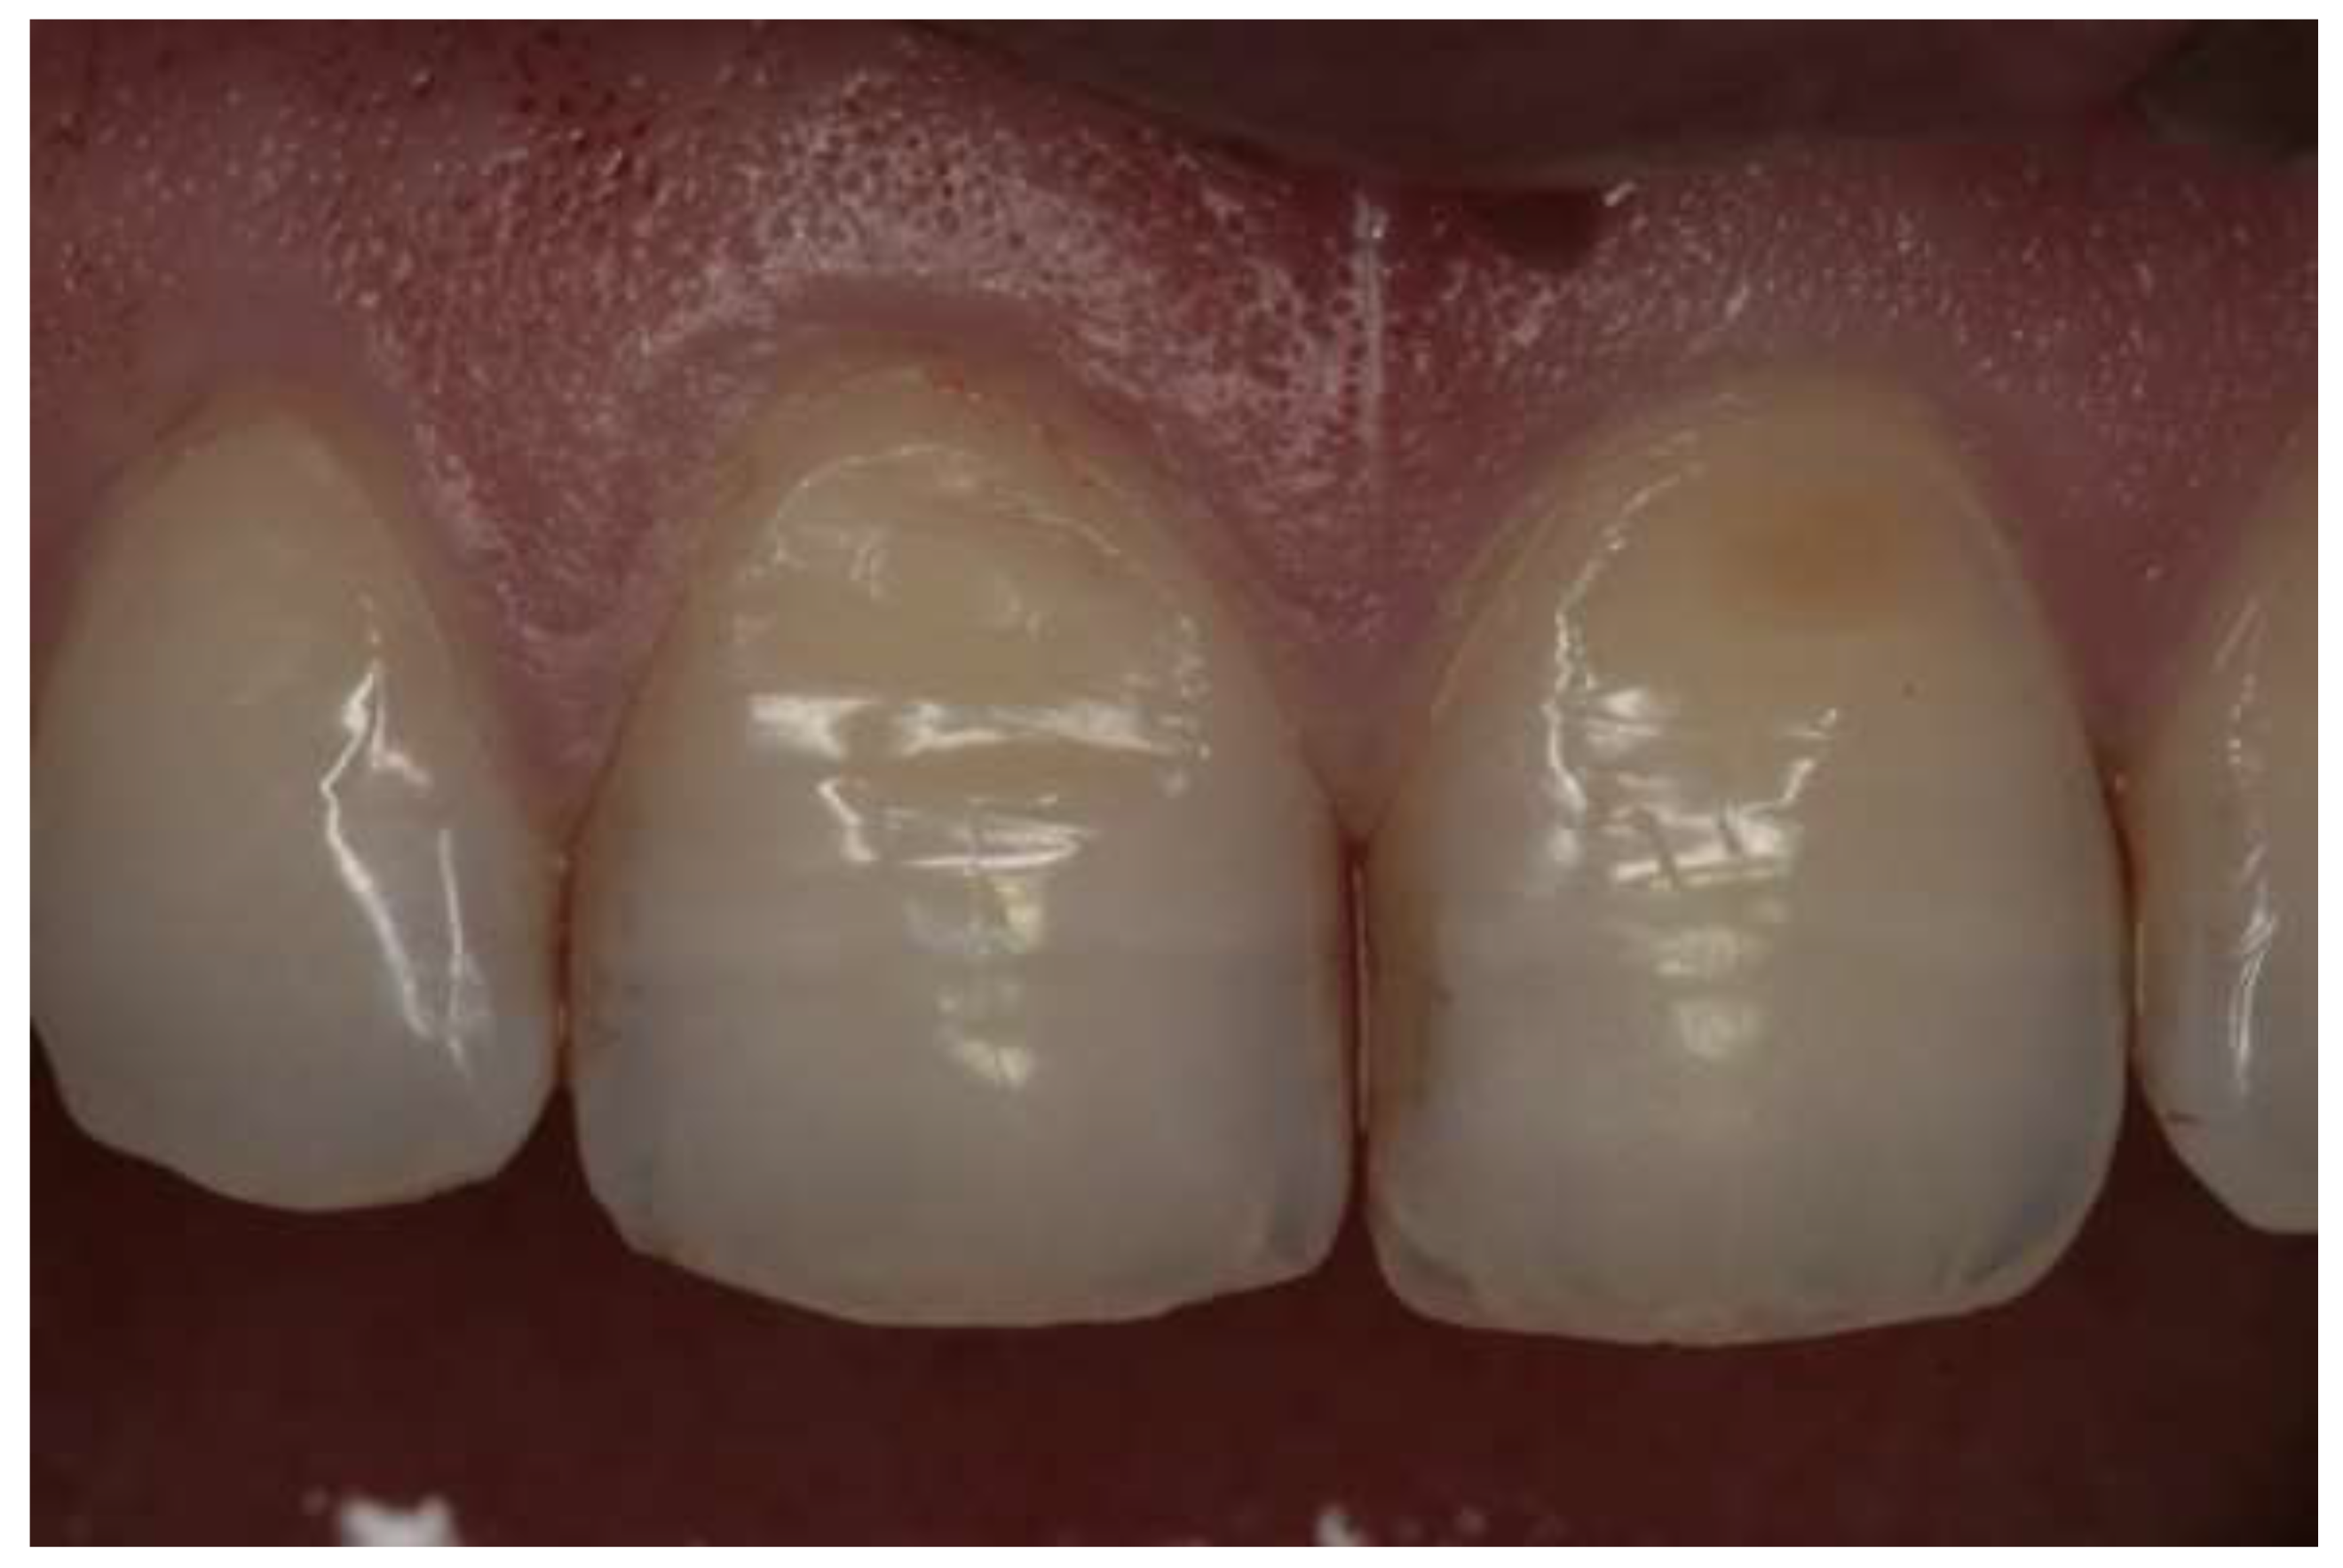

- Grade 0: no erosive changes;

- Grade 1: initial loss of enamel texture;

- Grade 2: visible loss of hard tissues under 50% of the surface; and

- Grade 3: visible loss of hard tissues over 50% of the surface.